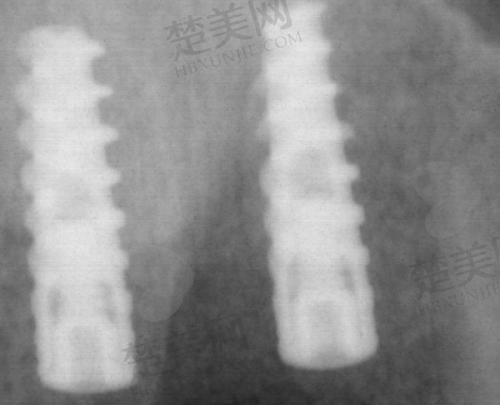

有个真实的实例,65岁的李老师全口牙齿掉完,戴了近10年假牙,导致牙槽骨萎缩,假牙都没法固定了。他去了好几家口腔医院,都说需要植骨。后来听说西安中诺口腔医院的“立得用”种植牙不用植骨,就去试了试。结果从开始检查到做完种植牙手术,总共不到半天时间,李老师就重新“长”出了一口好牙。种完牙后,他看起来比之前年轻了不少,咀嚼功能也修复正常了,一直夸中诺口腔的“立得用”种植技术好。